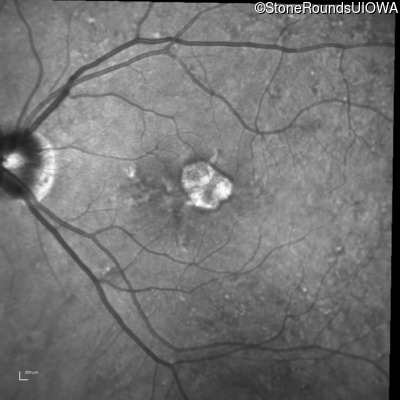

Infrared Fundus Photograph - Right - 20/20 -2

Exemplar